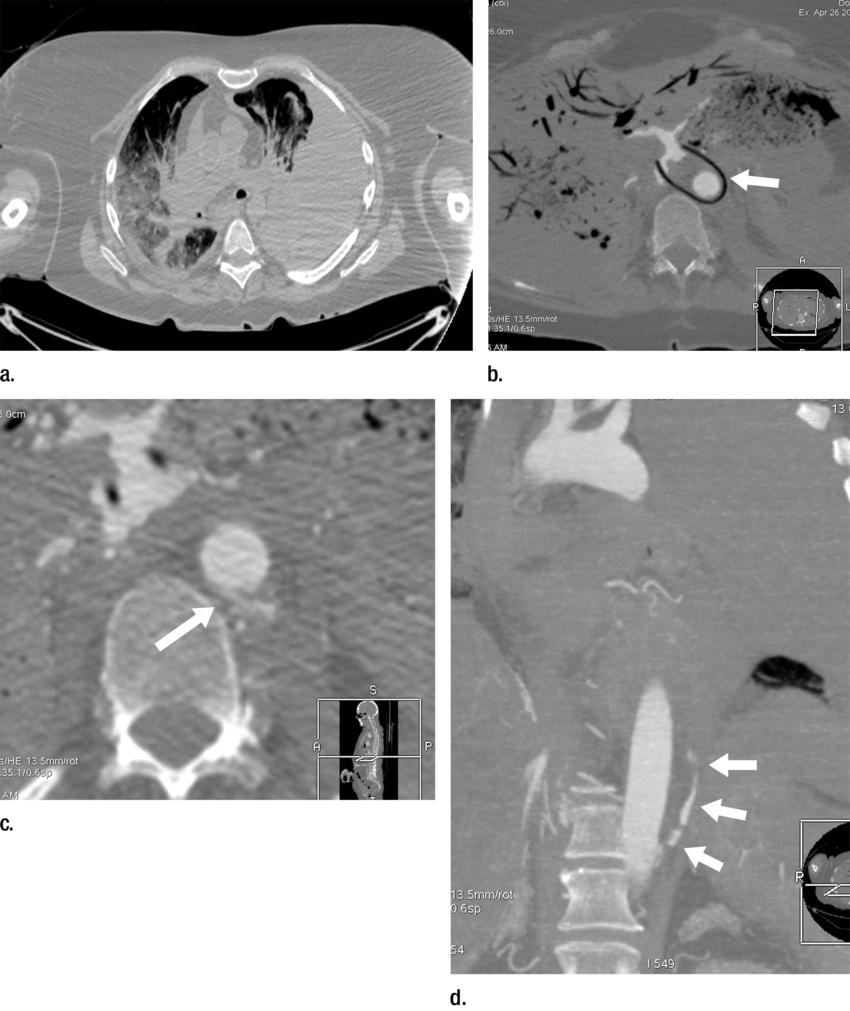

High-res (TIF) version

Figure 2. (a) Axial cervical postmortem CT scan and (b) zoomed section of the cricoid cartilage (box in a) of a 27-year-old woman who died of strangulation. Three-dimensional volumerendered reconstructions from cranial (c), left lateral oblique (d), and right lateral oblique (e) views. Postmortem CT scan clearly displays a displaced bilateral fracture of the cricoid cartilage (arrows). This finding is important because it proves the application of relevant force to the neck. It was difficult to demonstrate this finding at autopsy because anatomic preparation required extensive manipulation of the laryngotracheal region, which without postmortem CT would have been unclear regarding whether the fracture was caused by the preparation or was there before autopsy.